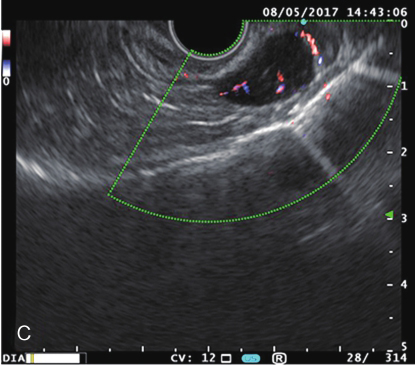

超声胃镜示:胃腔空虚,胃底可见隆起,约1.5cm,黏膜完整,上距贲门齿状线约4~5cm。超声:7.5~12MHz探查病变处第1~3层连续完整,第4层内可见一圆形低回声,界限清楚,约15.6cm×9.9mm大小,中心可见高回声斑点,可见血流信号,弹性成像显示,较硬。胃镜诊断:胃底肌层肿物(考虑 GIST)(图1)。

图1超声胃镜检查

A.肿物胃镜下表现;B、C.肿物超声胃镜下表现